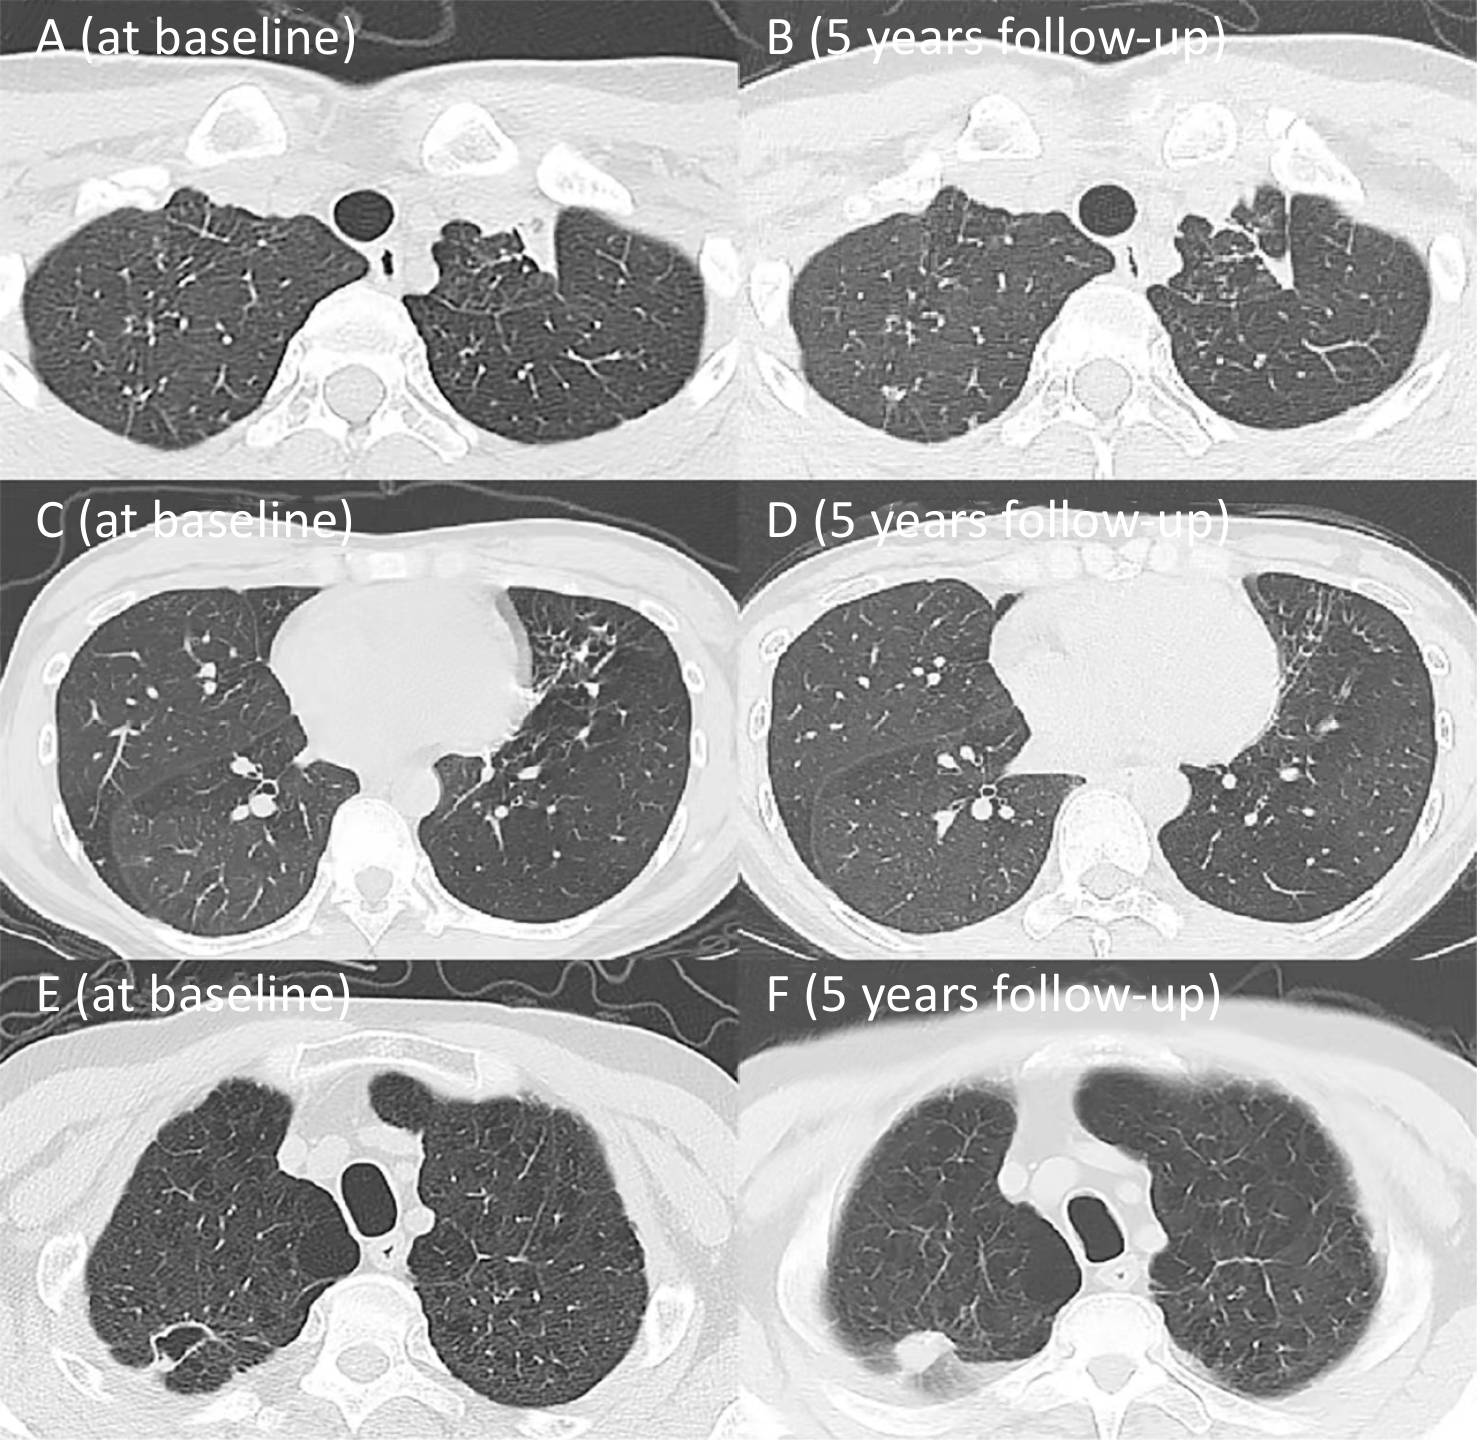

Figure  4.  Two representative cases of airflow obstruction: non-smoker and smoker. (A−D) Comparison of chest CT at initial test and the 5-year follow-up in the non-smoker. (E−F) Comparison of chest CT at initial test and the 5-year follow-up in the smoker.

• At the 5-year follow-up, the 9 patients with airflow obstruction had a mean age of 54.7 ± 13.5 years, including 6 males. Among them, four (all male) had a smoking history, with a median smoking exposure of 35.0 pack-years (IQR: 26.3−62.5). The mean FEV1/FVC ratio was 56.26% ± 9.23%, with mean FEV1 and FVC of 1.65 ± 0.75 L, and 2.84 ± 0.98 L, respectively. Chest CT imaging of these 9 patients revealed a variety of abnormalities: one female patient with a destroyed left lung and underwent lobectomy, and one male patient with a long-term history of coal dust exposure, presenting typical pneumoconiotic micronodular lesions (Cases 8−9). The remaining 7 cases predominantly exhibited imaging features such as air trapping, emphysema, and small airway disease. Three non-smoking middle-aged patients (Cases 1–3) primarily exhibited significant air trapping on chest CT without other notable abnormalities, suggesting that their airflow obstruction was mainly caused by small airway disease secondary to TB. Meanwhile, the other four older patients with long-term smoking histories (Cases 4–7) showed coexisting emphysema and small airway disease on imaging, indicating that their airflow obstruction likely resulted from the combined effects of smoking and prior TB infection. Representative chest CT images of a middle-aged non-smoking female (Case 1) and an older smoking male (Case 4) are presented in Figure 4. Notably, four of these patients (aged < 60 years) maintained persistent airflow obstruction over the 5-year follow-up period (Table 5).

Case 1: A female patient with no smoking history was diagnosed with pulmonary TB at 30 years of age. Initial chest CT demonstrated multiple patchy opacities with diffuse mosaic attenuation in both lungs. Lung function test revealed airflow obstruction, with FEV1% pred of 50.20%, FEV1/FVC ratio of 59.50%, and DLCO% pred of 69.90%. At the 5-year follow-up, chest CT demonstrated scattered residual fibrocalcific nodules in both lungs, with no significant improvement in the diffuse mosaic attenuation. Lung function showed a decline in FEV1% pred to 46.4%, and FEV1/FVC ratio to 52.63% (A−D).

Case 4: A male patient with a 67 pack-year smoking history was diagnosed with pulmonary TB at the age of 56. Initial chest CT revealed a cavitary lesion in the right upper lobe accompanied by bilateral emphysema. Lung function tests demonstrated airflow obstruction, with FEV1% pred of 29.70%, FEV1/FVC ratio of 54.02%, and DLCO% pred of 22.90%. At the 5-year follow-up, the cavity had resolved, but bilateral emphysema remained. Lung function further declined, with FEV1% pred of 26.20%, FEV1/FVC ratio of 45.08% (E−F).